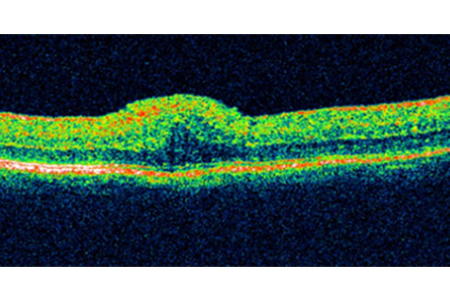

A Case of Central Serous Retinopathy (CSR) showing fluid collection under Neurosensory Retina